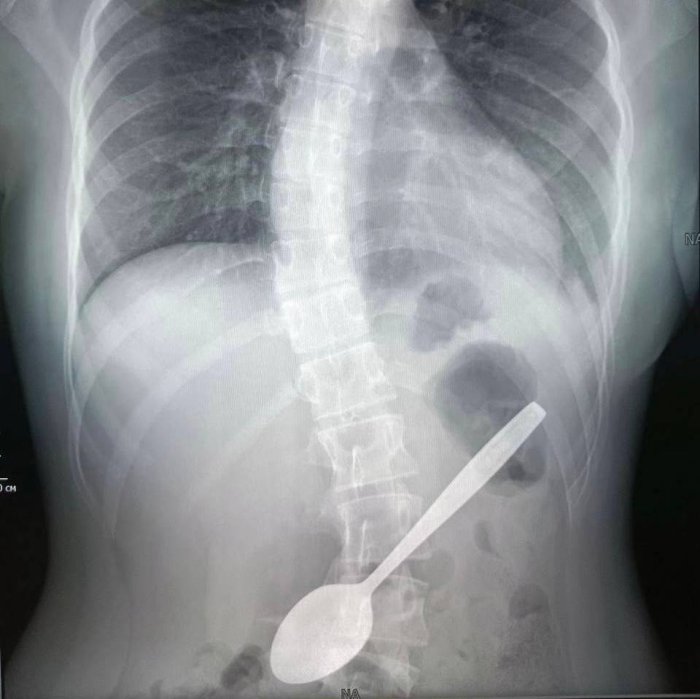

Врачи ДКЦ им. Рошаля извлекли из желудка школьницы чайную ложку

14-летняя девочка пыталась достать ей кусок яблока, застрявший у ней в горле. Как она ухитрилась проглотить столовый прибор — неизвестно.

Медики сделали юной пациентке рентгенографию органов брюшной полости и приступили к хирургической операции.

«Ложка стояла в распорку: тонкой частью упиралась в стенку желудка, а широкой частью уходила в луковицу двенадцатиперстной кишки.

Эндоскопической петлей мы извлекли ложку из луковицы двенадцатиперстной кишки, а после эндоскопическими щипцами по типу "крысиный зуб" протянули ее до глотки.

После этого хирургическим зажимом мы полностью извлекли инородное тело из организма ребенка.

Операция длилась около часа и прошла успешно», — рассказала врач-эндоскопист Дарья Степаненко.

Сейчас девочка чувствует себя хорошо и уже дома.